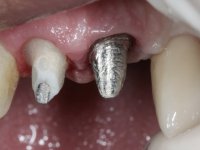

Endodontic treatments were performed and a metalic non screwed intra radicular post was placed on tooth 1.1. An alginate impression was made for laboratory confection of a reinforced acrylic provisional bridge, with teeth 1.1 and 2.2 as abutments and 2.2 as a pontic. After preparation of tooth 1.1 and root preparation of 2.1, the bridge was relined in mouth with self-polymerizable acrylic using a metal post for further retaining the prepared root canal on 2.1. Tooth 2.2 was cut at the gingival level to function as support. In the same session, the impression of the root canal of the 2.1 was made for the laboratory confection of a cast post and core. A double mixture technique with plastic tutor was used after previous canal vaseline with endodontic file and cotton. The provisional bridge was provisionally cemented and the cast post and core was made in the laboratory. Cast post and core cementation was made with resin-reinforced glass ionomer cement and the provisional bridge had to be readjusted to the new situation by removing the post at the site of 2.1. After careful surgical planning, a dental implant was placed, simultaneously with extraction of the root of tooth 2.2. The provisional bridge was placed by resting on the healing screw placed in the implant. The respected osteointegration period was 12 weeks, during which the provisional bridge was relined twice. After complete maturation of hard and soft tissues, definitive impressions were made. The gingival retraction technique was applied with an impregnated retraction cord and impression was performed using double mixture, open tray impression technique. A custom precious metal abutment implant was prepared in the lab, along with 3 metal caps to be used as infrastructures for the metal ceramic crowns. Particular care was taken in the confection of the cervical finishing line of the implant abutment, in order to follow the soft tissues emergence profile. Proof of infrastructures was done in the mouth being evaluated clinically and imagiologically. Collection of color information was done by the ceramist at the office. Ceramic was applied in the laboratory and the finished work was placed in the mouth after approval by the patient. Definitive cementation was made with resin-reinforced glass ionomer cement, and the first crown to be cemented was that of the implant, to facilitate removal of the excess.